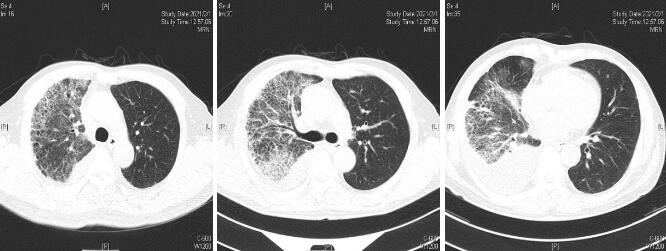

1 资料与方法男性,62岁,因“咳嗽咳痰伴发热5 d,气促2 d”于2021年1月26日就诊本科。1月21日患者淋雨后出现咳嗽咳痰,咳淡黄色黏痰,多次发现痰中带血,量少,性质黏稠,不易咳出,伴有发热,Tmax37.5℃,服用阿奇霉素、对乙酰氨基酚症状未见好转。1月24日出现气促,不能平卧,端坐稍缓解,无畏寒寒战等其他不适,1月26日就诊急诊科,查体:T 36.2℃,P 123次/min,R 35次/min,BP 146/94 mmHg (1 mmHg=0.133 kPa),SPO2:90%(FiO2:40%)。神志清醒,半卧位。双肺呼吸音粗,右中上肺可闻及湿性啰音,右下肺呼吸音弱,左肺未闻及明显干湿性啰音。心率123次/min,律齐,各瓣膜听诊区未闻及病理性杂音。四肢肌力正常,双下肢凹陷性水肿,余查体无异常。实验室检查:白细胞15.96×109/L; 血小板85×109/L; 中性细胞比率95.7%;C反应蛋白>200 mg/L; 降钙素原15.05 ng/mL; 血气:pH 7.345;二氧化碳分压30.4 mmHg; 氧分压60.3 mmHg; 碳酸氢根16.2 mmol/L; 乳酸4.58 mmol/L; 生化:钠129 mmol/L; 尿素9.80 mmol/L; 白蛋白26.00 g/L; 总胆红素51 μmol/L; 直接胆红素25 μmol/L; BNP 7384 ng/mL; 凝血:凝血酶原时间15.10 s; 国际标准化比值1.37;纤维蛋白原9.95 g/L; 肺部CT提示双肺多发渗出及实变,以右肺为重,右侧胸腔少量积液。综上检查SOFA评分为7分,依据脓毒症3.0诊断标准[2],考虑“脓毒症-重症肺炎”收入EICU住院治疗。既往高血压病史10余年,血压控制在110/70 mmHg。个人史抽烟30余年,10根/d。在海口某小区任保安,无出岛旅居史,无接触及饲养动物史。

| 图 1 1月26日首次就诊胸部CT平扫 |